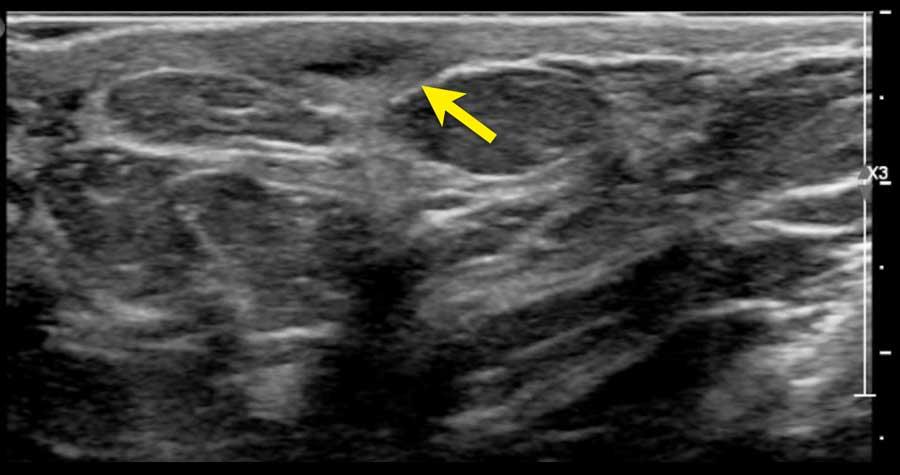

Gần đường giữa, các xương sườn chỉ được cấu tạo bởi sụn và chưa bị vôi hóa.

Sụn không tạo ra phản âm trắng ở mặt trước hay bóng cản âm phía sau.

Thay vào đó, một cấu trúc giảm âm được quan sát thấy phía trước phổi.

Không nên nhầm lẫn cấu trúc này với khối u vú.

Thoạt nhìn, cấu trúc này có thể trông giống u xơ tuyến vú khi hình ảnh xương sườn được cắt trên mặt phẳng ngang.

Khi xoay đầu dò, sẽ nhận thấy đây là một cấu trúc dài liên tục với phần xương sườn đã vôi hóa.

Tổn thương nhỏ dưới da là một nang bì (dermoid cyst), sẽ được thảo luận ở phần sau.